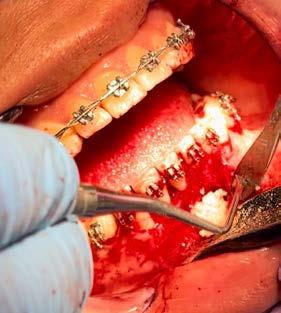

material de relleno del gap

Implante inmediato en sector estético con PRGF-ENDORET como único material de relleno del gap

implante hacia palatino para evitar la proximidad a la tabla vestibular implica que en muchos casos entre el implante y la tabla ósea vestibular se genere un espacio conocido como “gap” en el implante postextracción inmediata. Este espacio en ocasiones debe ser rellenado para evitar el colapso posterior estableciéndose como norma general que en aquellos casos en los que el grosor de la tabla vestibular oscile entre 1 y 2 mm y el espacio del gap es menor de 2 mm la capacidad regeneradora propia del alveolo haría que no fuese necesario el relleno del gap con ningún tipo de material para que se produjese la regeneración ósea en el mismo.13 Otros casos en los que la cortical sea de menor grosor o el gap de mayor distancia (o la combinación de ambos factores) debe ser rellenado el espacio con un biomaterial que permita la regeneración más favorable del defecto.13,14 Dentro de los materiales de relleno que pueden utilizarse, en la literatura internacional tenemos: hueso autólogo, hueso desmineralizado desecado y congelado, hueso mineralizado desecado y congelado, xenoinjerto, fosfato tricálcico y plasma rico en factores de crecimiento.15,16 El empleo de PRGF-Endoret para el manejo de este gap en el implante postextracción es un enfoque biológico y totalmente autólogo basado en las propias proteínas y señales celulares del paciente que nos garantiza buenos resultados a largo plazo, según las referencias publicadas en la literatura internacional donde se ha confirmado el potencial

que para estas situaciones altamente comprometidas es una excelente opción.18-24 En el presente caso clínico mostramos un paciente rehabilitado con un implante postextracción

inmediata y carga inmediata en el sector estético manejando el gap con la utilización exclusiva de PRGF-Endoret.

Caso clínico

Presentamos el caso de un paciente varón de 47 años, que acude a la consulta dental por presentar dolor, movilidad y fístula en la pieza dental 11. Este caso, fruto de un traumatismo previo, tuvo que ser endodonciado y posteriormente realizada sobre el mismo una apiceptomía, para abordar un quiste apical residual que no terminaba de evolucionar de forma favorable. El trabajado de rehabilitación posterior se llevó a cabo con una reconstrucción con poste y una carilla cerámica. Tras varios años, el diente ha comenzado de nuevo con los síntomas anteriormente descritos por lo que se sospecha la presencia de una fractura radicular. La

radiografía panorámica inicial para el diagnóstico nos aporta una imagen radiolucida entorno al ápice del diente en posición 11 ( Figura 1 ). Para conocer mejor el alcance de la lesión y las opciones terapéuticas de las que disponemos se lleva a cabo un cone-beam en el que se puede objetivar de forma precisa el defecto apical al diente. Este defecto es circunferencial y está dejando una reabsorción casi completa de la tabla ósea vestibular y parcial de la palatina, con un grosor de 1.9 mm, como vemos en el corte seccional (Figura 2). Si observamos la medida total en la zona media del incisivo dentral, necesitamos cubrir una anchura aproximada de 8 mm por lo que el implante que coloquemos irremediablemente dejará un gap, que según los protocolos quedará en vestibular. Utilizando una plataforma estándar de 4.1 mm el gap a rellenar será prácticamente de 4 mm según las medidas que nos

posible sobre los tejidos blandos y sobre el hueso remanente (Figura 5 y 6). Procedemos posteriormente a realizar una secuencia de fresado adaptada al lecho postextracción, alargando el alveolo con las fresas apicalmente y hacia palatino, donde se producirá el anclaje del implante. Con el lecho preparado colocamos el implante, quedándonos en vestibular el gap esperado de aproximadamente 4 mm como podemos ver en la

Figura 7. La utilización de un implante de longitud mayor y la inclinación hacia palatino nos permite lograr la estabilidad primaria necesaria para poder llevar a cabo una carga inmediata del implante. Una vez finalizada la inserción colocamos el transepitelial unitario para trabajar sobre el mismo generando la prótesis provisional de carga inmediata. Esta pieza intermedia (implante-prótesis) nos permite el uso de una interfase,

Una vez colocado el implante y el transepitelial para elaborar la prótesis de carga inmediata se realiza el sellado del gap vestibular, en este caso empleando únicamente PRGF-Endoret. El procedimiento es igual que

9 y 10. Relleno del gap con PRGFEndoret, situando un coágulo recién activado de la fracción 2 en el fondo del alveolo y posteriormente un tapón de fibrina para la zona más superior (fracción 1 activada y retraída).

para el sellado de un alveolo postextracción, colocándose un coágulo de PRGF-Endoret recién activado de la fracción 2 (con alta liberación de factores de crecimiento) y sobre el mismo un tapón de fibrina autóloga sellando la zona más cercana al reborde alveolar (Figura 9 y 10). No se utilizan puntos de sutura para evitar el colapso del tejido blando del alveolo, además que por la adhesividad de la fibrina se mantiene en

posición sin necesidad de suturarla. A los 3 días podemos colocar la corona confeccionada de carga inmediata y vemos en la imagen antes de hacerlo la correcta epitelización de los tejidos blandos alrededor de la tapa de protección del transepitelial (Figura 11).

ya cicatrización parcial del tejido blando. Estando en esta fase de cicatrización temprana, podemos además adaptar los tejidos blandos a la emergencia que queremos darle al incisivo central (Figura 12 y 13 ). La prótesis provisional se mantiene durante 3 meses. Transcurrido este tiempo se confecciona sobre el mismo transepitelial la prótesis definitiva. De esta manera, las uniones epiteliales formadas entre el tejido gingival periimplantario y el transepitelial no se rompen, garantizándose un mejor sellado a este nivel, evitándose problemas como la mucositis periimplantaria. El paciente continúa en seguimiento posterior durante 2 años. En las imágenes clínicas se observa la estabilidad de los tejidos blandos (Figura 14 y 15). En este momento del seguimiento se realiza un nuevo cone-beam en el que vemos la anchura lograda a nivel crestal, con una regeneración completa de la tabla vestibular (Figura 16).